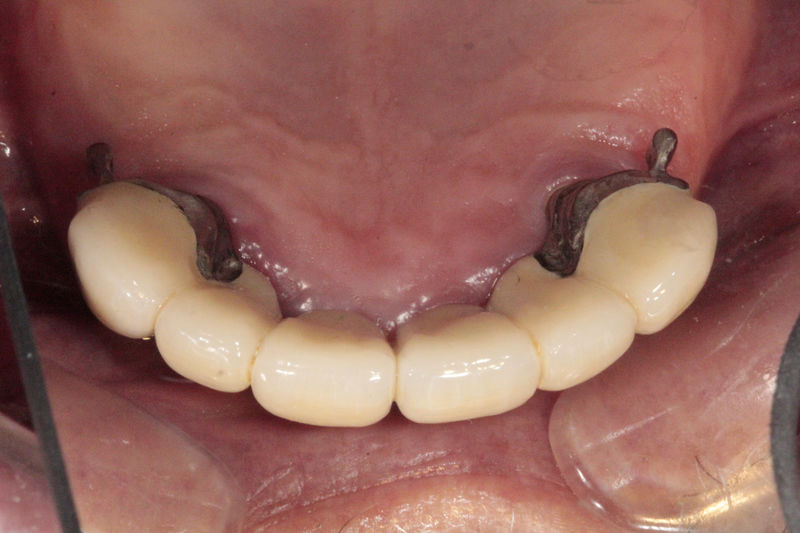

Restauraciones fabricadas en el laboratorio los cuales se usan para reemplazar dientes ausentes usando dientes, coronas y/o tejidos blandos como soporte y que pueden y deben de ser removidas para su limpieza. Para poder enviar el caso al laboratorio se toman impresiones utilizando materiales de impresión o técnicas modernas digitales.

Restauraciones fabricadas en el laboratorio los cuales se usan para reemplazar dientes ausentes en toda una arcada usando implantes y/o tejidos blandos como soporte y que pueden y deben de ser removidas para su limpieza. Para poder enviar el caso al laboratorio se toman impresiones utilizando materiales de impresión o técnicas modernas digitales.